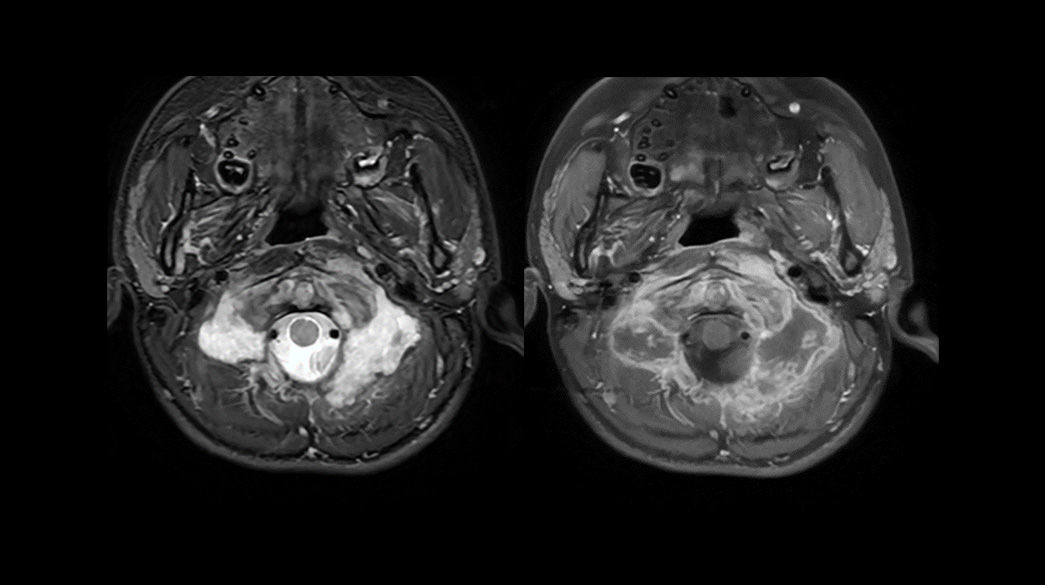

Diagnostic confidence and consistency

AIRRecon-DL1040-x-585

Learn more ico-caret-right

MR image reconstruction with AIR™ Recon DL

AIR™ Recon DL has revolutionized MR imaging with deep-learning based image reconstruction increased image quality, reduced scan time and improved SNR.